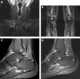

Bone marrow edema syndrome